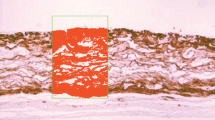

Measurements of CM thickness and collagen content in streptavidin-stained sections (reported previously ([42]) were made by superimposing three rectangular regions of interest (ROIs) per disc, one anterior, one middle, and one posterior. Each ROI had dimensions of 0.625 mm × 0.4 mm (= 0.25 mm2). A grid containing 40 μm × 40 μm cells was superimposed on the ROIs (Fig. 1) and the number of cell intersections in the grids that hit collagen within the ROI was registered. Mean residual collagen content (% of baseline) and CM thickness (mm) were determined for each disc. H&E stained sections were used to better identify the surrounding tissues (Fig. 2). For macrophage and endothelial cell counts, identical ROIs were used and all positive cells were counted within each ROI and the mean per disc was calculated.

Photomicrograph showing the 40-μm-cell grid superimposed on the ROI (stained green) overlying the disc, which is stained in red/brown with an Avidin‐biotin‐HRP reaction. The horizontal borders of the ROI are set to include the total width of the membrane disc. Methods used to measure collagen content and immunostained cells are listed in the “Methods” section